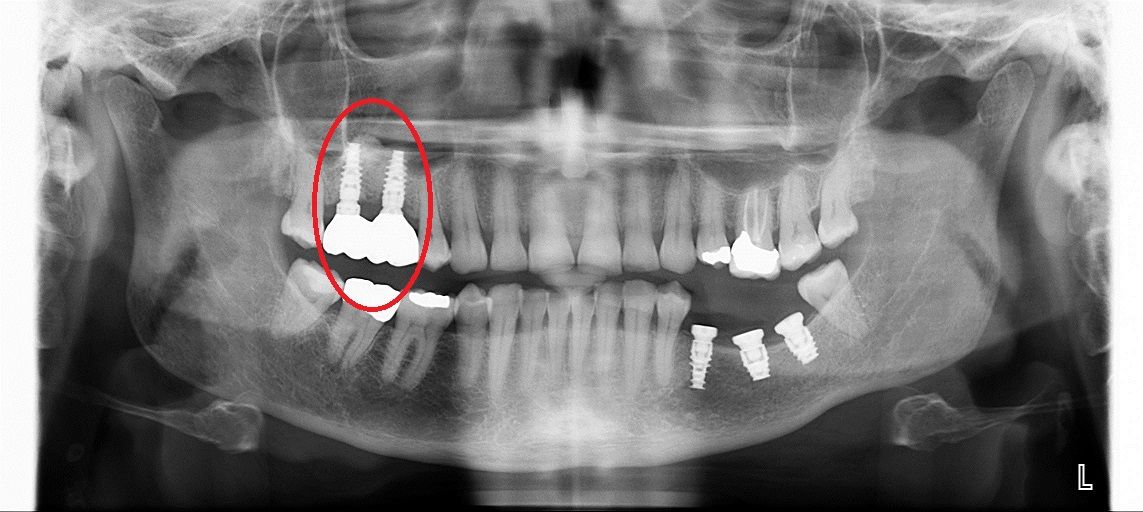

• до синус-лифтинга

• после синус-лифтинга

• после установки имплантатов в верхнюю челюсть

• коронки установленные на имплантаты